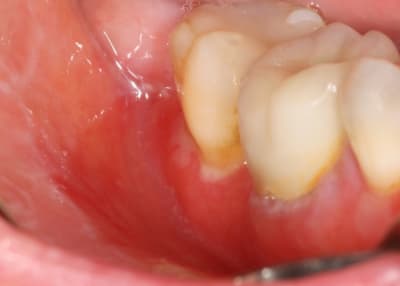

désolé de venir encore perturber votre post mais je voudrais profiter de vos compétences.

patiente vue cet après-midi :

27 ans

grande période de stress

l'état d'ulcération de la gencive ne semble pas passer malgré la reprise du brossage.

D'emblée je pense pas à un truc de malade mais plutôt à des traumatismes locaux faits par le patiente lui-même avec une brosse à dent toute pourrie avec des poils pliés et des problèmes d'hygiène de départ suite à fatigue ou soirée alcoolisée ou les muqueuses sont parfois très fragiles.

Est-ce possible d'après toi qui connait la personne ?

Conclusion = quelque chose de bénin, 1 semaine de bain de bouche et réévaluation

brossage régulier en constante amélioration depuis deux semaines

brosse à dent Inava Parodontie neuve (c'est pas une brosse chir mais c'est pas la plus dure non plus)

prescription de piasclédine depuis un mois

bains de bouche quotidiens

certes l'état général de la gencive est beaucoup mieux mais je ne m'explique pas cette disposition symétrique des ulcérations et le fait que cela ne semble pas vouloir disparaitre.

Pr Dentiste 57 je repond comme Canin (encore une fois) meme si les lesions ont l'air symetriques et qu'en generale il y a tjrs un coté ou on s'acharne plus, en secteur 1 sur la gencive adherent y'a comme un dérapage de brosse a dent .

pas d'ATCD ?

pas de médoc ?

pas d'autre lésions ?

Tartre ? car ont dirait un truc commme ca sur 16 ?

si alcool a gogo il peut aussi avoir deficience vitaminique ?

Si clope et alcool et stress on peut envisager un debut de GUNA meme si cela n'en a pas l'air pr l'instant.

clope et stress: OK

alcool , je ne pense pas : cette patiente est saine

elle m'a dit être très fatigué et prendre depuis 1 mois des compléments vitaminiques.

pour la GUN je ne trouve pas que cela y ressemble

BOn ben ce qu'on sait

jeune 27 ans

stress

tabac

dure depuis au moins 2 semaines

(pas de grossesse ?, post partum ?)

- GUN mais c'est pas un aspect typique

- Neutropénie cyclique mais en générale c'est connue depuis longtps(Les manifestations commencent au cours de la deuxième enfance., ça s'en va et ca reviens dixit Claude Francois.

ma collaboratrice a eu ma patiente en consultation, gencive purulente, papilles légèrement décapitées.

alors c'est bien une GUN non ?